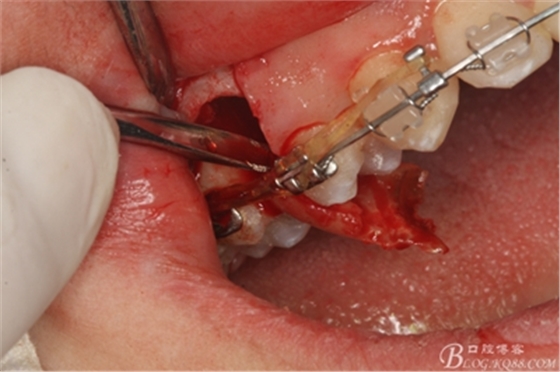

圖11.仔細(xì)考慮之后,在14頰側(cè)做垂直切口,切口長(zhǎng)度僅達(dá)膜齦聯(lián)合處,做小切口。

圖12. 做垂直切口+齦溝內(nèi)切口,形成角形瓣,暴露出15根面。